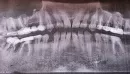

Год мне лечили гранулему в соседнем 6-м зубе. В итоге, когда я пришла ставить коронку на пролеченный зуб, мне сказал доктор, что из-за сильной стираемости зубов мне нужно делать встречное протезирование (минимум 16 зубов), предварительно 1,5 – 2 года походить в брекетах. Но после КТ выяснилось, что гранулемы есть ещё под тремя зубами, что есть перфорация корня зуба. Мне предлагают удалить 3 зуба (2-х у меня уже нет).

Я планирую беременность, и меня пугают, что все может обостриться и нанести вред. Я не знаю, как поступить. Насколько опасны гранулемы и вероятен риск их обострения? И как быть с повышенной стираемостью зубов?

Прикрепленые фото

Действительно, мы имеем много проблем в полости рта, и беременность в такой ситуации повлечёт обострения и негативное лечение на всем сроке. Грануляция или киста — это воспалительный процесс, который имеет свойства обостряться, как правило, при сниженном иммунитете, простуде и так далее. Также стираемость зубов говорит о необходимости протезирования.